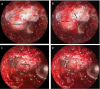

Background: Invasion of the CS is one of the limiting factors for total resection for PitNet tumors with cure rates less than 30%. Extended approaches may be considered in selective and well-studied cases of secreting adenomas.

Method: We describe the key steps of the endoscopic transcavernous approach for functional pituitary adenomas with a video illustration. The surgical anatomy is described along with the advantages and limitations of this approach.

Conclusion: A detailed knowledge of CS anatomy and familiarity with this surgical approach acquired in the laboratory is essential. Proper instrumentation is critical to decrease the risks of vascular injury.